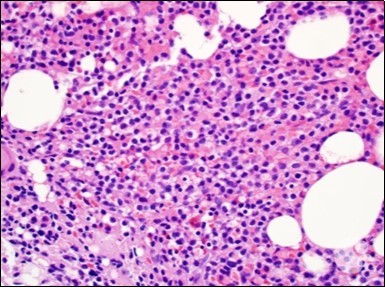

The classic hairy cell is medium sized with a magnitude of 10-14µm. The moderately abundant or variable cytoplasm may be transparent or mildly basophilic. The cellular surface with the characteristic serrated perimeter depicts innumerable fragile or stout extensions of cytoplasm ,particularly discernible on the phase contrast and electron microscopy. The cytoplasm may exhibit vacuoles with occasional azurophilic granules4. The nucleus may be elliptical or reniform, folded or indented with a coarse, reticulated or a finely dispersed chromatin and inconspicuous nucleoli along with infrequent mitosis. Bone marrow aspiration or bone marrow trephine biopsy may be inadequate for diagnosis in 30%-50% individuals4. The trephine sections of the bone marrow may depict a characteristic interstitial pattern of leukaemic infiltration. Generally the bone marrow is hyper-cellular, though it may be hypo-cellular in 10-15% individuals4. The leukaemia cell ingress may be diffuse or partial, although diffuse infiltration is frequent. The partial variety of leukaemic dissemination may be ineptly categorized with an indeterminate differentiation from the uninvolved marrow. The malignant insertions may initially emerge as miniature, undefined, cellular loci. The formalin fixed, paraffin embedded sections may elucidate a crystalline zone or a “halo” appearance of the cells with a circumscribed nucleus on account of the plentiful cytoplasm4. The cellular margins may be intertwined. Fixation of bone marrow smears with Zenker’s fixative may demonstrate a retracted cytoplasm of the hairy cells with a consequent disconnected structure. The bone marrow in the absence of a malignant process may be hypo-cellular or hyper-cellular. Reticulin stains may delineate an enhanced accrual of broad, dense reticulum fibres surrounding the aggregates of leukaemia cells with the fibrous circumlocution of individual malignant cell and fibrotic extensions into the abutting, uninvolved bone marrow4.

The leukaemia cells may enunciate a characteristic immune phenotype, crucial for a confirmatory diagnosis. The peripheral blood mononuclear B cell population may display a kappa or lambda light chain restriction. The phenotype of classic hairy cell leukaemia may be delineated by concurrent, immune reactive CD19+ CD20+,CD 11c+, CD25+, CD103+ and CD123+. An intensely immune reactive CD200+ and a non reactive CD27- antigen may be present2, 4. Evaluation of a trephine bone marrow biopsy and bone marrow aspirate may define the degree of tumour infiltration. A dry tap on account of prominent bone marrow fibrosis may be elucidated at preliminary diagnosis. A decline in the normal haematopoiesis may account for a hypo-cellular marrow in 10% instances. Gradation of cellular infiltrating of the leukaemia within the bone marrow may be appropriately investigated with immune –histochemical stains2, 4. Immune staining for CD20+, annexin 1 and VE1 (a BRAF V600E stain] may validate the diagnosis and precisely analyse the extent of malignant bone marrow infiltration[8]. Determination of BRAF V600E mutation may be critical in therapeutically non responsive individuals with applicable standard therapy or in instances of multitudinous reoccurrences[9]. Deploying inhibitors of BRAF V600E gene may be efficacious in patients impervious to approved therapy. The mutation necessitates a comprehensive scrutiny of the implicated individuals with a sensitive molecular assay which may discern up to < 10% of the hairy leukaemia cells appearing in the peripheral blood smears or bone marrow aspirates diluted with peripheral blood or aspirates elucidating a dry tap[2,4]. Allele specific polymerase chain reaction (PCR) or a next generation sequencing may be optimally employed to circumvent false negative outcomes. If the leukaemia cells are sparse or if particularly sensitive & efficacious molecular techniques are not accessible, the application of appropriate immune histochemical stains to the bone marrow biopsy such as a BRAF V600E mutation stain (VE1) may detect the hairy cells and conclusively diagnose the condition[2,4,10]. Figure 1, Figure 2, Figure 3, Figure 4, Figure 5, Figure 6, Figure 7, Figure 8, Figure 9, Figure 10, Figure 11, Figure 12, Figure 13, Figure 14.

Figure 3.HCL: hairy cells dispersed within the native architecture(19).

Figure 4.HCL: hairy cells with widely spaced nuclei(20).

Figure 8.HCL: widely disseminated hairy cells within the bone marrow trabaculae(24).

Figure 9.HCL: hairy cells within a bone marrow trephine biopsy(25).